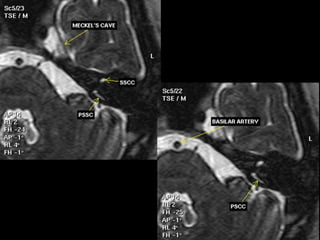

IAC MRI Anatomy and Search Pattern :

3D CISS sequence (thin axial high T2 sequences)

Review axial images superior to inferior

Look at CN V and Meckel’s cave Look at Petrous Apex

Look at the Cerebellopontine angle Look at the IAC and evaluate it’s origin

Notice CN 7 & 8 in the IAC and

their close relationship to AICA

More inferiorly, evaluate the cochlear

and vestibular nerves